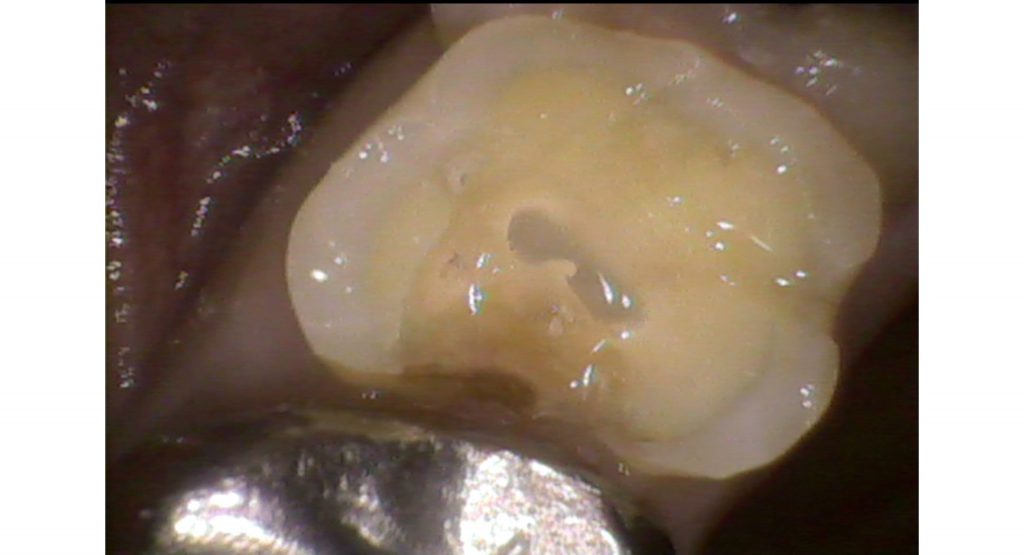

抜髄処置 Case2

虫歯菌(ミュータンス菌)によりエナメル質が溶け神経まで虫歯菌が進行すると神経が炎症を起こし痛みを伴います。症状としては、冷たい物や温かい物がしみる、何もしなくても痛いと感じることがあります(この症状があったからと言って必ず神経を取るわけではありません)。神経まで虫歯が進行しているにもかかわらず治療せずに放置すると、根の先に膿がたまり根の先の顎の骨が溶けることがあります。